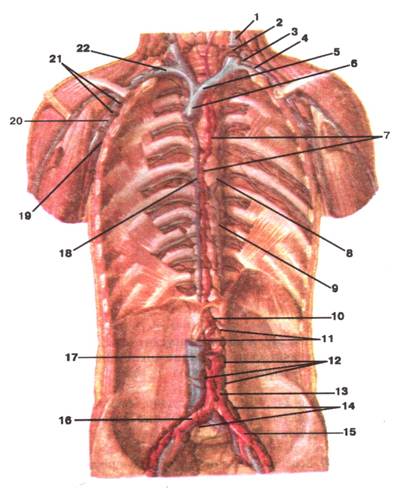

Малюнок А. 5 – Ductus thoracicus. Загальні клубові вузли. Поперекові вузли.

Вигляд спереду:

1 -vena jugularis interna (sinistra); 2 -arcus ductus thoracici; 3 -angulus veno‑sus; 4 -truncus subclavius (lymphaticus); 5 -vena brahiocephalica sinistra; 6 -vena cava superior; 7 -ductus thoracicus; 8 -vena hemiazygos accessoria; 9 -vena hemiazygos; 10 -cisterna ductus thoracici; 11 -trunci intestinales; 12 -nodi lymphatici lumbales; 13 -aorta; 14 -nodilymphaticiiIiaci communes; 15 -arteria iliaca communis sinistra: 16 -arteria iliaca communis dextra; 17 -vena cava inferior; 18 -vena azygos; 19 -vena axillaris; 20 -arteria axillaris; 21 -nodi lymphatici axillares; 22 -vena axillaris dextra